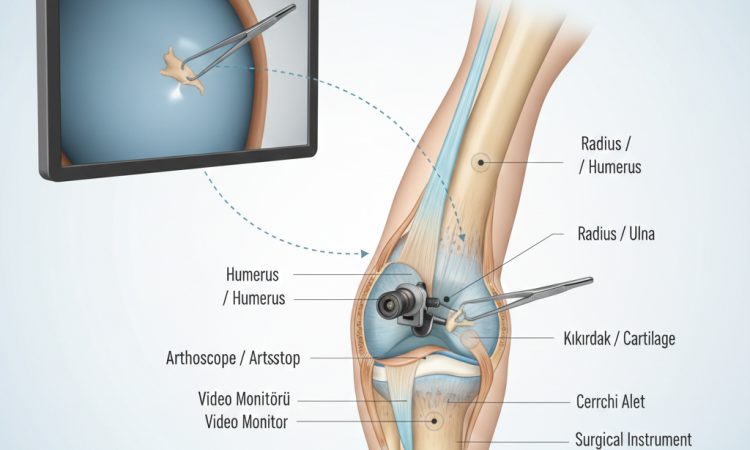

Dirsek eklemi, günlük hayatta bardağı ağzımıza götürmekten ağır yük taşımaya kadar her an kullandığımız kompleks...